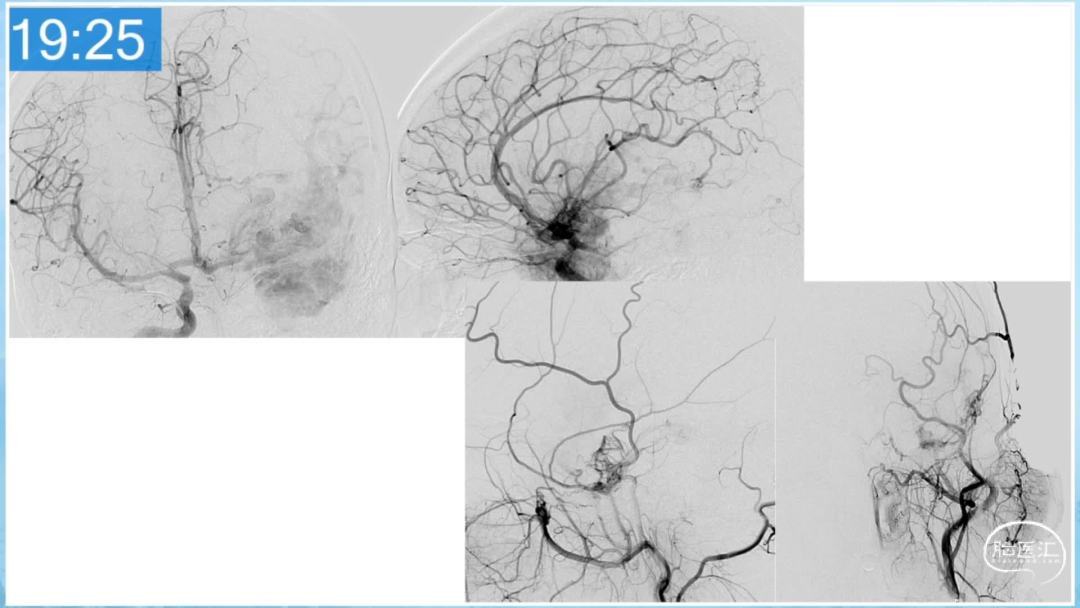

本期为大家特别分享:空军军医大学唐都医院邓剑平教授的精彩会议内容《颅内动静脉畸形的复合手术治疗》,欢迎大家阅读和分享!

合理的复合平台下的综合治疗,针对每一个病变对应不同方法安全性分析,不预设、不排斥,每种技术发挥到最佳,互相保障。